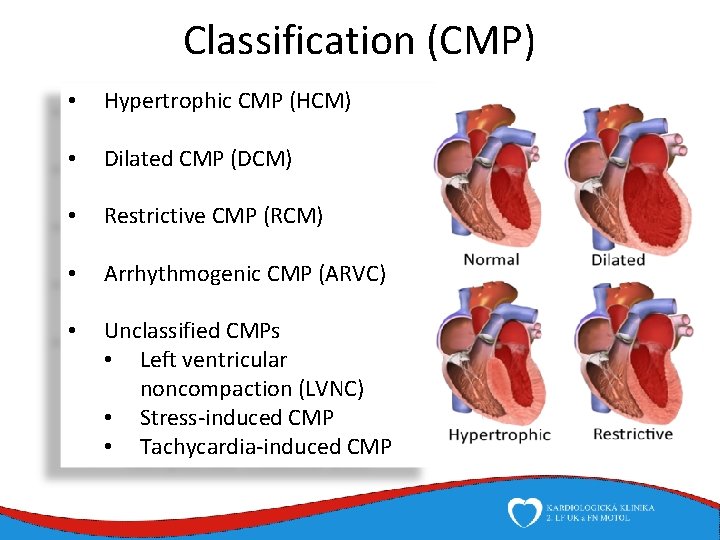

Classification (CMP) • Hypertrophic CMP (HCM) • Dilated CMP (DCM) • Restrictive CMP (RCM) • Arrhythmogenic CMP (ARVC) • Unclassified CMPs • Left ventricular noncompaction (LVNC) • Stress-induced CMP • Tachycardia-induced CMP